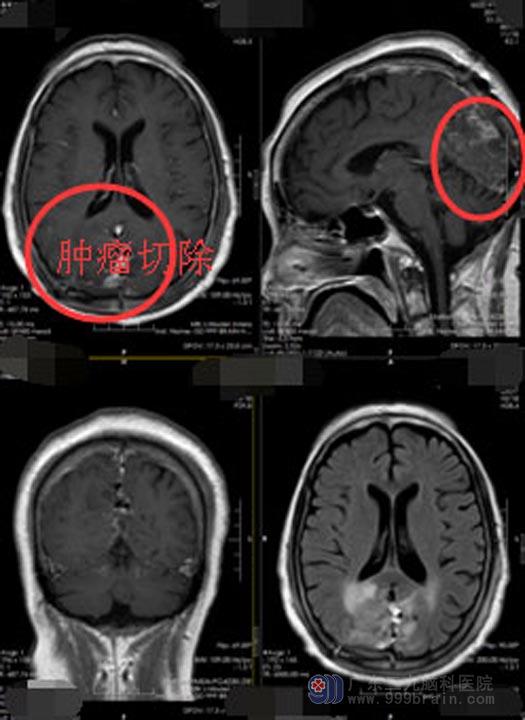

控制好李阿姨的血压和血糖后,鲁明主任带领神经外五科的手术团队在全麻下为李阿姨行“双侧枕叶大脑镰窦旁脑膜瘤切除+矢状窦修补术”,术中可见肿瘤质韧,血运丰富,与脑组织边界不清,有部分粘连,肿瘤内邻矢状窦、大脑镰,基底位于大脑镰向两侧生长,侵及上矢状窦颌下矢状窦;分块切除肿瘤,肿瘤大小约5.5cm×5.0cm×5.0cm。

术后第三天,李阿姨的生命体征平稳,对答切题,四肢自主活动,复查头颅CT提示肿瘤全切,未出现明显的脑水肿。病理结果示:非典型脑膜瘤,WHOⅡ级。